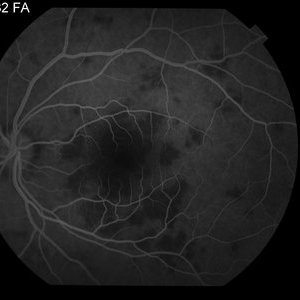

AMPPE

Apr 29 2014 by David W. Faber, MD

24-year-old female presented with central blurry vision for 3-5 days. Vision : OD 20/20, OS 20/100

Photographer: Jodi Schiele, Rocky Mountain Retina Consultants, Salt Lake City, Utah

Condition/keywords: acute multifocal placoid pigment epitheliopathy (AMPPE)